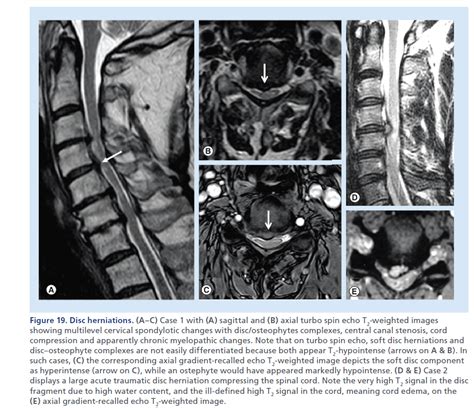

Degenerative Diseases of the Spine | Radiology Key